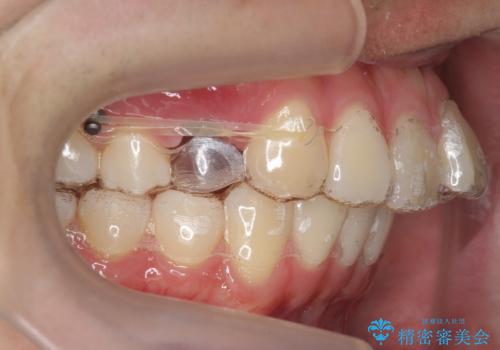

出っ歯の治療 インビザラインで抜歯矯正 親知らずを使用した矯正

- 出っ歯を主訴に来院。

上の小臼歯を2本抜歯しています。

そのかわり、上の親知らずを生かしており、歯の本数は減っていません。

矯正用ミニスクリューを使用しています(インプラント矯正)。

奥歯の歯ならびのずれが大きく、親知らずを抜いてすべて後ろに下げるか、手前の歯を抜いて前歯を下げるかの2択でした。

時間はかかりましたがしっかり前歯を下げて治療しています。